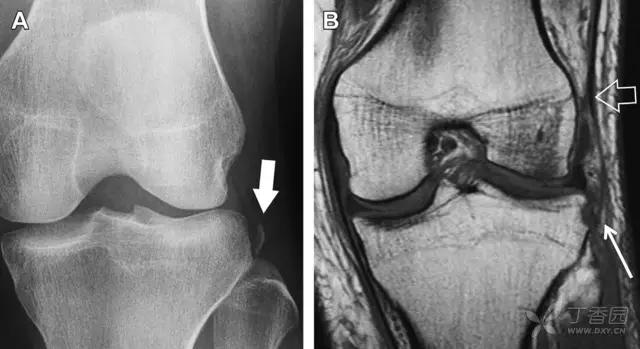

一位足球运动员的 Segond 骨折。A 正位片示关节线下方胫骨外侧皮质撕脱(箭头)。B MRI 冠状位 T1 加权像示附着于髂胫带的骨折碎片(空箭头)(来源:Radiol Clin N Am 53 (2015) 737–755,YU,Ohio)

一位足球运动员的反向 Segond 骨折。A 正位片示关节线处的胫骨内侧见一细小骨折片(箭头)。B MRI 冠状位 T1 加权像示骨折片出现在内侧副韧带关节囊附着处(方框)(来源:Radiol Clin N Am 53 (2015) 737–755,YU,Ohio)